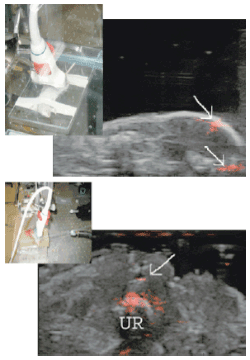

در این مرحله به‌کمک «میکروسکوپ فتوآکوستیک» و تلفیق تصاویر آن با تصاویر به‌دست آمده از روش شناخته‌ شده‌ی مافوق صوت، غربالگری بهتر و سریع‌تر سرطان پروستات ممکن شد.

آن‌ها آنتی‌بادی‌های اختصاصی علیه گیرنده‌های HER2 - که در انواع خاصی از سرطان‌های پستان و پروستات زیاد می‌شوند - به نانوذرات متصل ساختند و سپس به‌کمک یک میکروسکوپ اختصاصی با تفکیک‌پذیری 500 میکرومتر، اتصال آنتی‌بادی به نانوذرات را تأیید کردند.

در این مطالعه، محققان از نانواستوانه‌های بلند طلا به‌طول 45 و قطر 15 نانومتر استفاده کردند. این استوانه‌ها دارای «رزونانس پلاسمون» در حدود 750 نانومتر هستند.